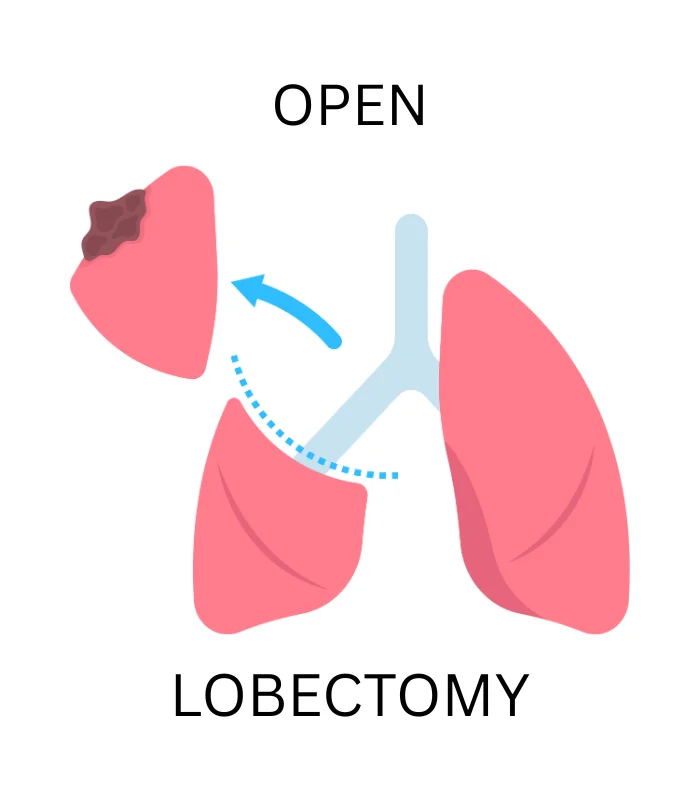

Popular Treatments